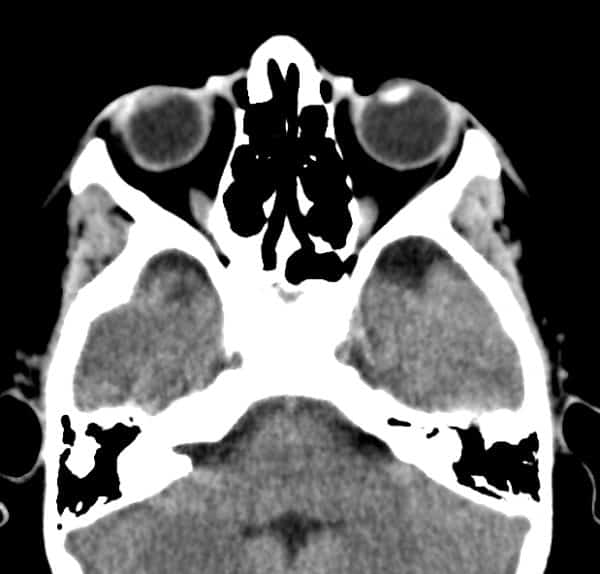

Đục thủy tinh thể trái

Chấn thương nhãn cầu

» Thông tin: Nam giới – 10 tuổi.

» Lâm sàng: Mù mắt phải sau chấn thương.

# Thủy tinh thể phải giảm tỷ trọng do phù nề.